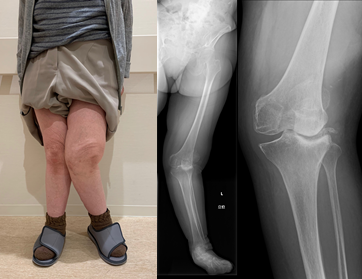

高度X脚